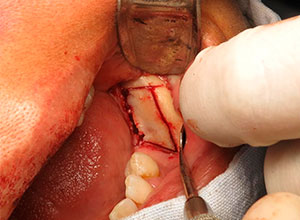

Se irriga profusamente la zona dadora con suero fisiológico y suturamos la incisión con catgut crómico. Una vez obtenido el injerto se preserva envuelto en una gasa húmeda con suero fisiológico isotónico y se remodela con la ayuda de unas pinzas gubia hasta adaptarse a la forma del defecto a injertar. La zona dadora puede prepararse mediante la perforación de la cortical externa con el fin de obtener un sangrado que facilite la revascularización del injerto.

Con el Injerto óseo modelado, se procede a colocar en el defecto óseo, fijándolo con tornillos, para asegurar su estabilidad.

Se espera de 6 a 8 meses para lograr la integración del injerto, se descubre el área para la colocación de implantes dentales.